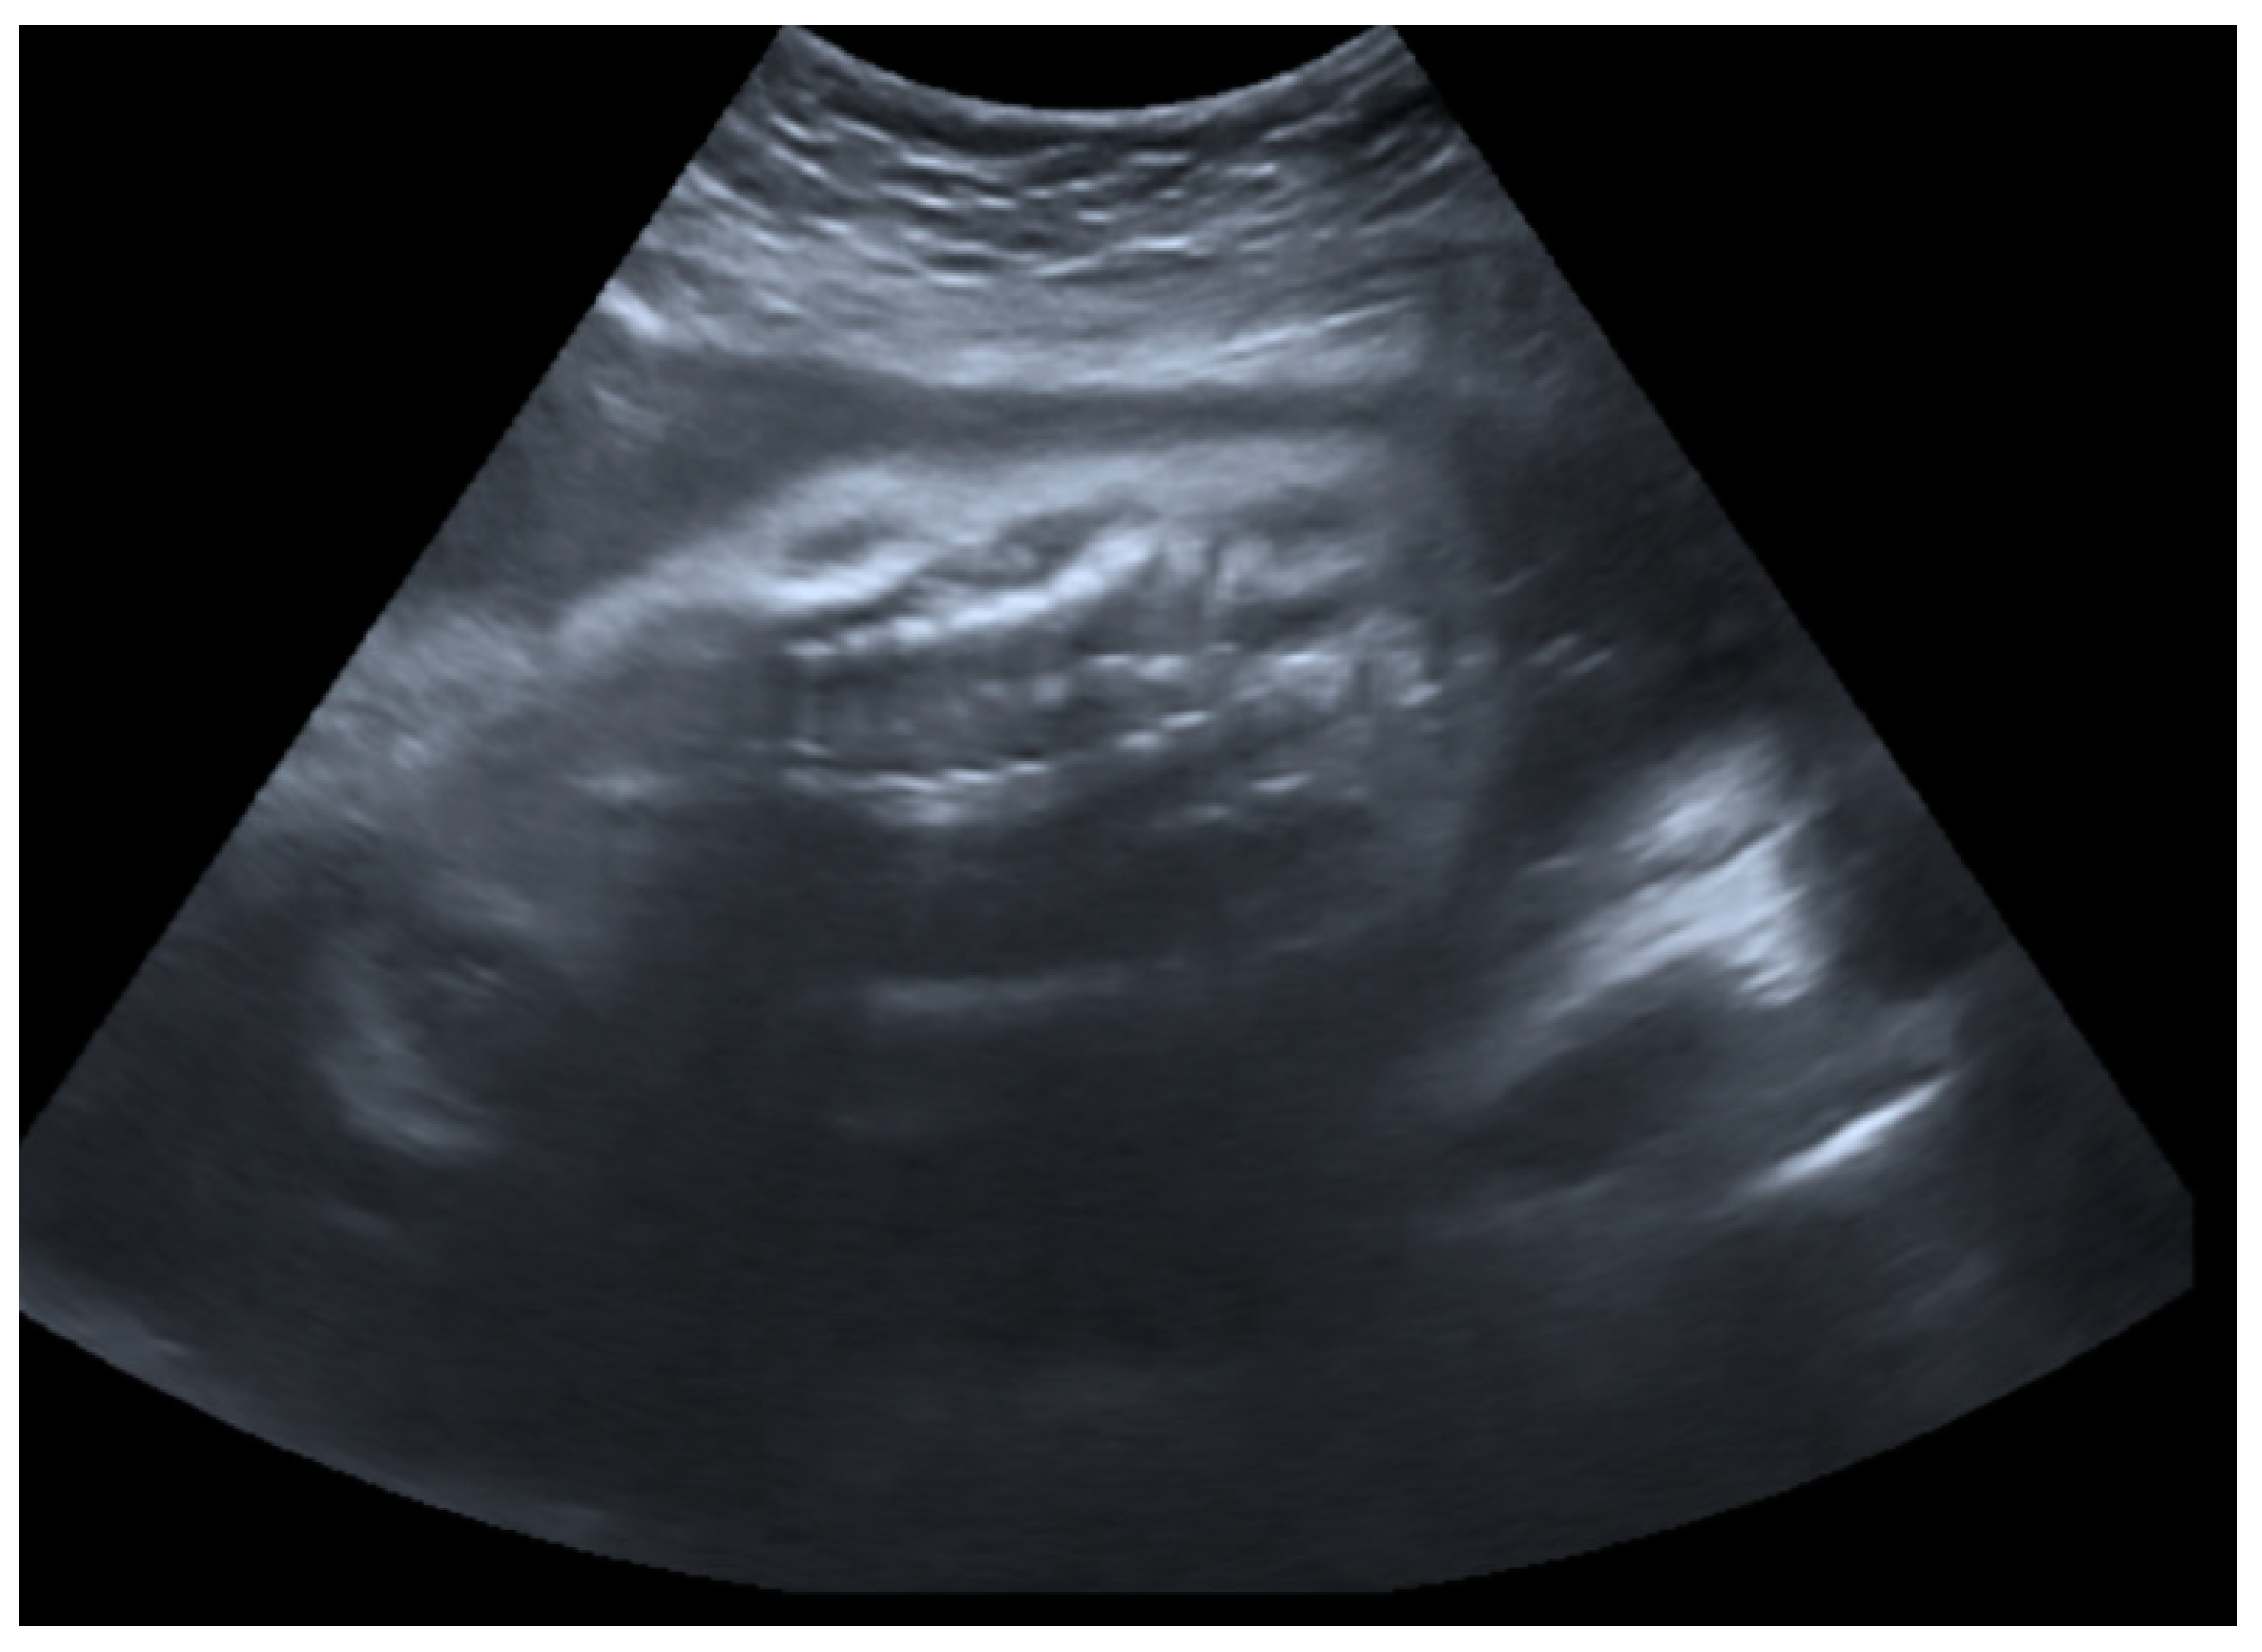

2.1. Prenatal Findings and Further Pregnancy Care